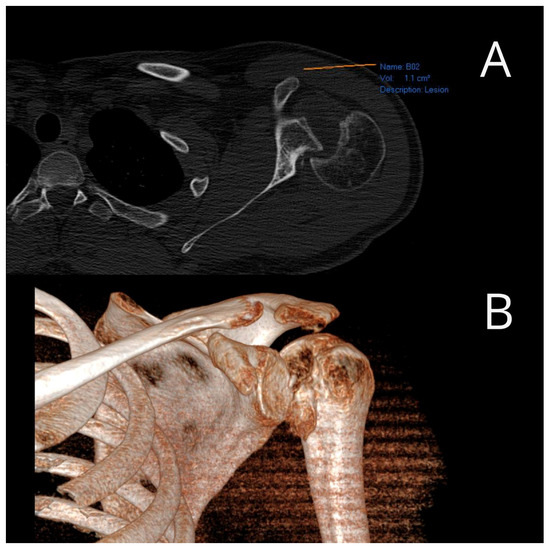

The average value of Constant’s point scale for the operated shoulder was 84.14 (ranging from 50 to 93) (Table 1), indicating a good result. Postoperatively, a follow-up X-ray and CT scan were performed, which demonstrated the appropriate positioning of the allograft in all twenty patients (Figure 5).

Figure 5. Postoperative X-ray (A) and three-dimensional CT view (B) of the operated shoulder (photo from the personal archive of intraoperative photos of the author).